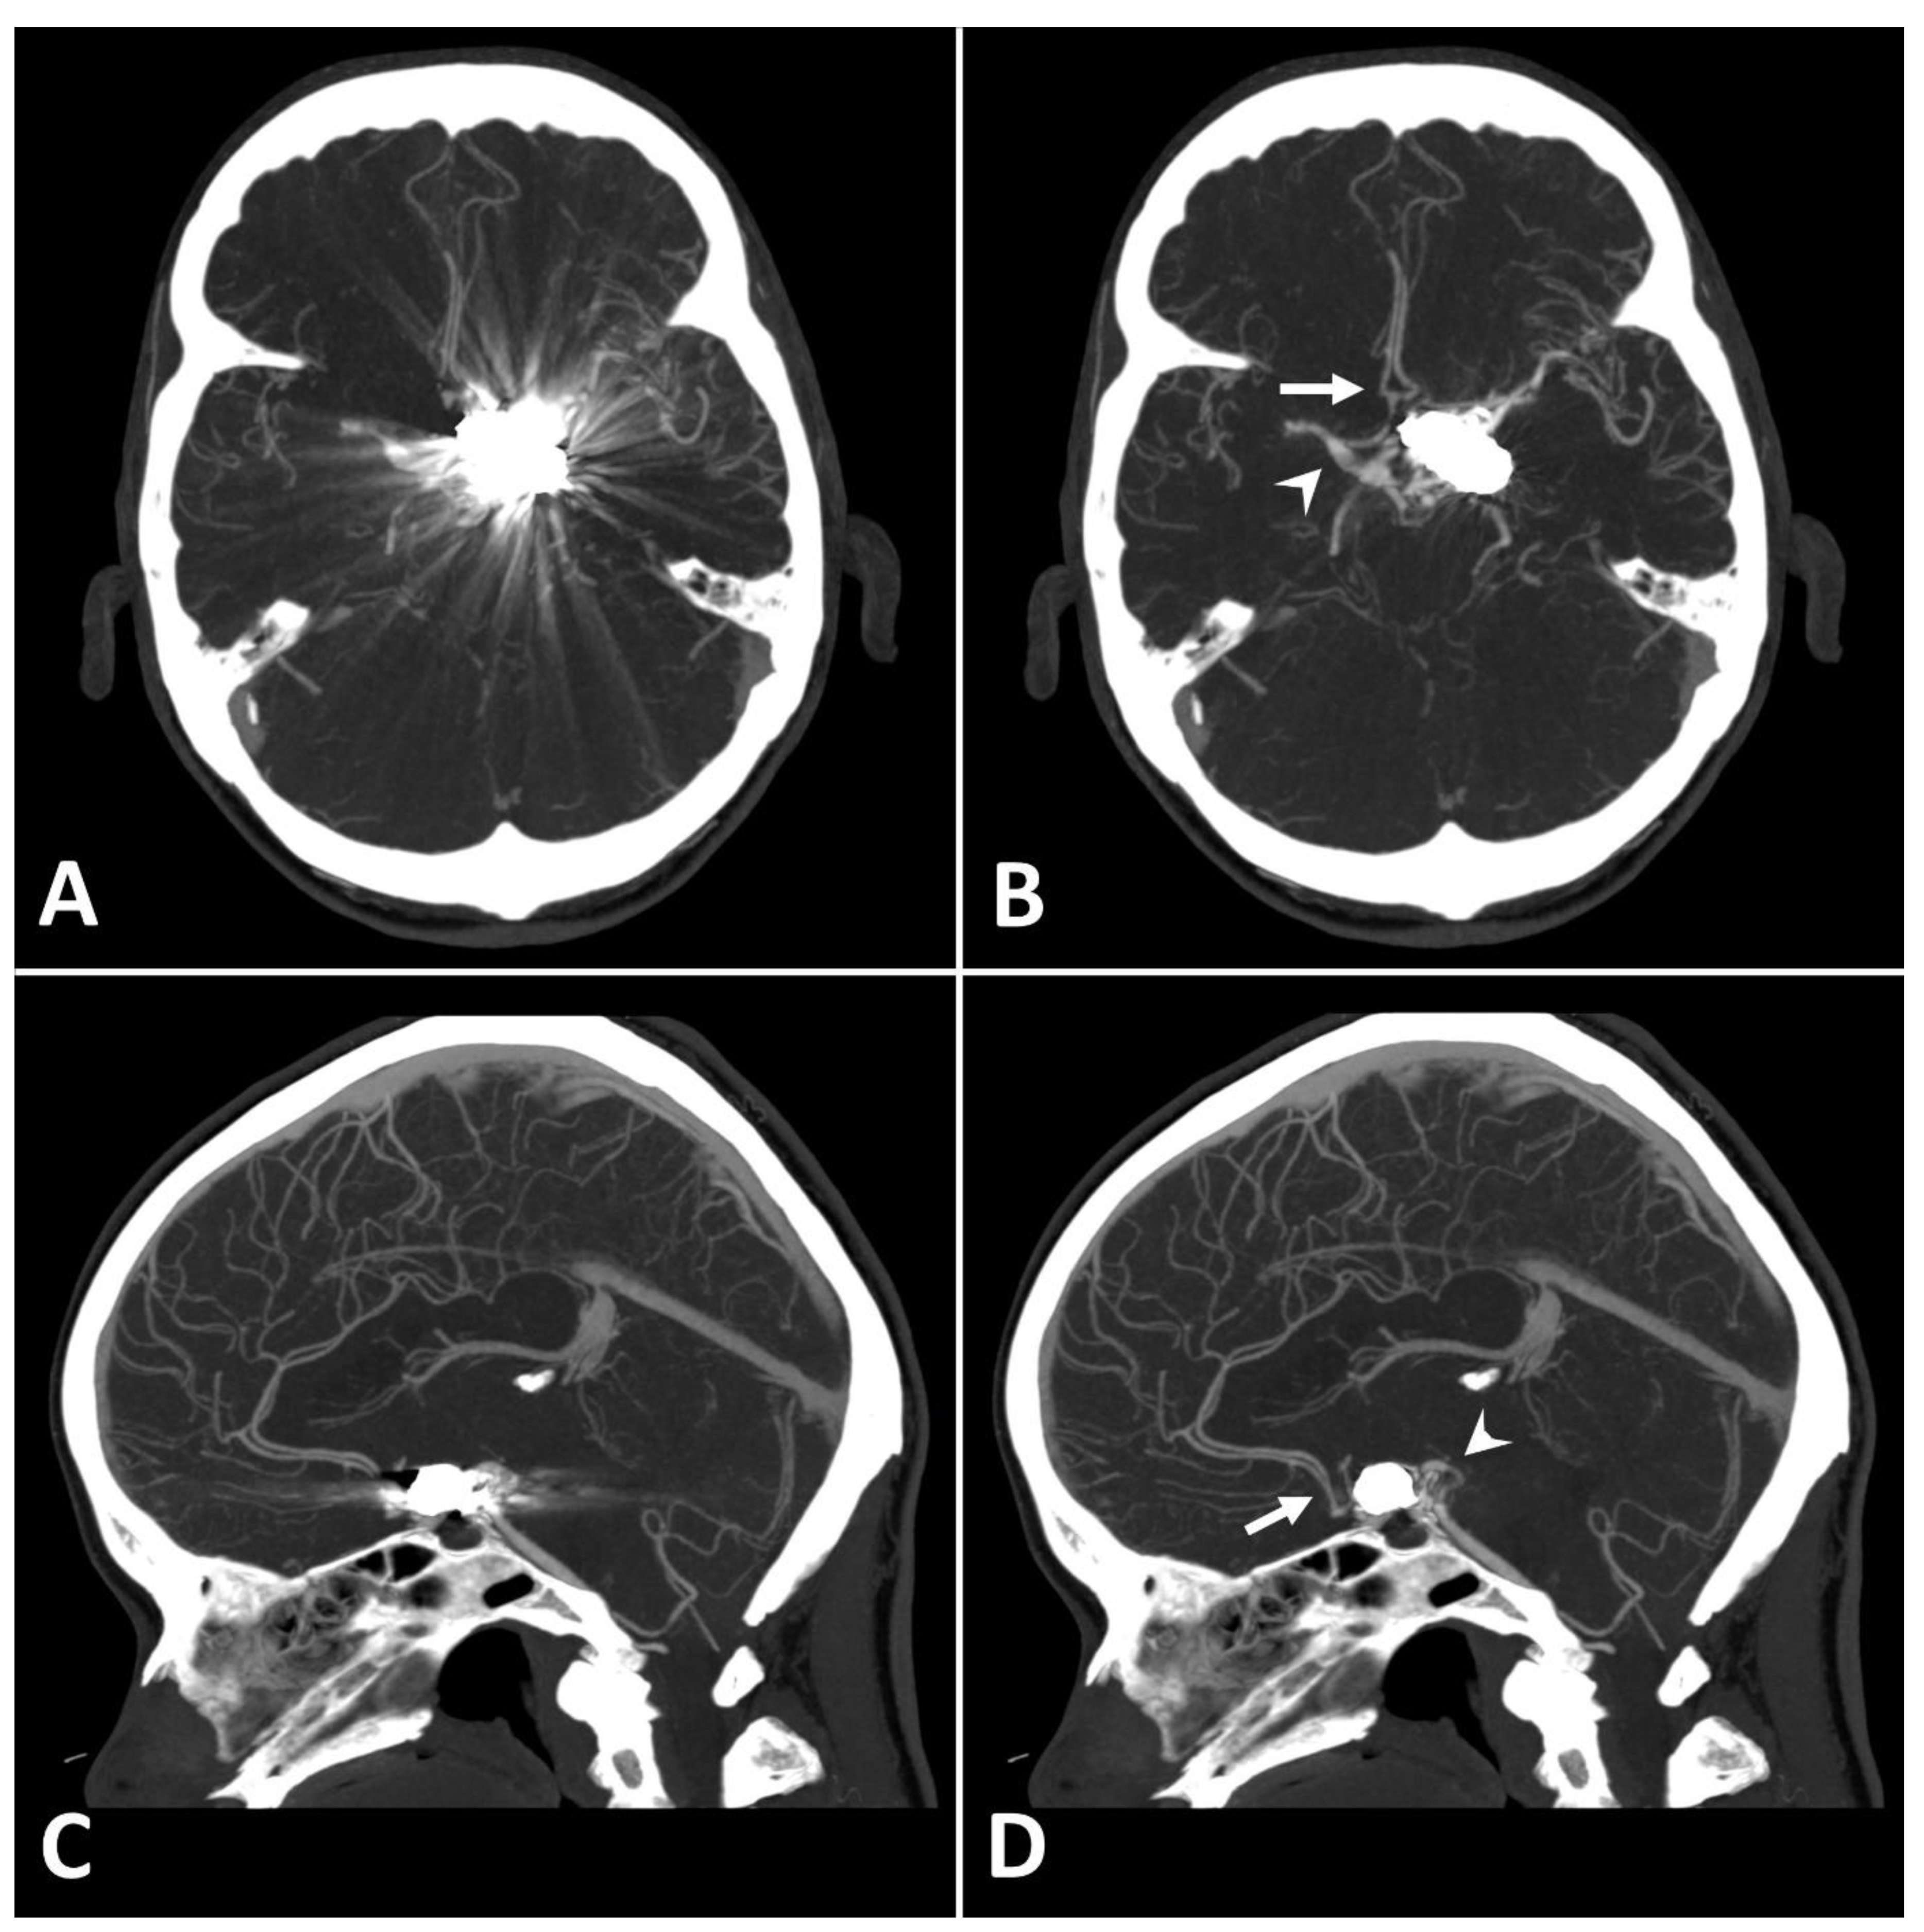

Metal artifact index (MAI) (which was considered to be the mean image noise) was significantly reduced in SEMAR images compared to standard images in close vicinity to (70.9 ± 22.1 vs. 331.8 ± 157.5, respectively) and more distant from the coil package (24.7 ± 6.7 vs. 52.4 ± 20.3, respectively; p < 0.001 each). Figure 2 and Figure 3 demonstrate significantly improved image quality and visualization of arteries after applying the SEMAR algorithm on images with coil-artifacts.

Figure 2.

Exemplary follow up UHR-CT-angiography in axial (A,B) and sagittal (C,D) plane without (A,C) and with SEMAR (B,D) of a 56-year-old female after intracranial coil-embolization of a left sided posterior communicating artery aneurysm. All images were reconstructed as MIP (Maximum Intensity Projection) with 12.5 mm slice thickness. SEMAR significantly improves image quality, even in vessels directly adjacent to the coil package like the anterior communicating artery (white arrow in (B)), the contralateral terminal carotid artery (arrowhead in (B)), the anterior cerebral artery (white arrow in (D)), and the posterior communicating artery (arrowhead in (D)).